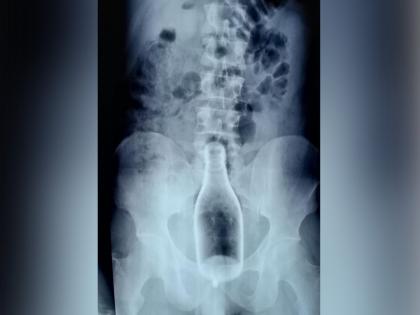

लॉकडाउनदरम्यान अनेक विचित्र घटना समोर आल्या. तळीरामांबाबतही अनेक आश्चर्यकारक घटना समोर आल्या. अशीच एक हैराण करणारी घटना तामिळनाडूच्या नागापट्टिनम जिल्ह्यातून समोर आलीये. आतापर्यंत तुम्ही काही लोकांच्या पोटातून केसांचा गोळा, नट-बोल्ट काढल्याचे ऐकले असेल. पण येथील एका व्यक्तीच्या पोटातून चक्क दारूची बॉटल काढण्यात आली. जी पाहून डॉक्टरही हैराण झालेत.

येथील एक 29 वर्षीय व्यक्ती 28 मे रोजी म्हणजे गुरूवारी पोटात दुखत असल्याची तक्रार करत नागापट्टिनम सरकारी हॉस्पिटलमध्ये दाखल झाली होती. पण जेव्हा त्याची तपासणी केली गेली तेव्हा डॉक्टरांनाही धक्का बसला.

शुक्रवारी 2 तास चाललेल्या सर्जरीनंतर या व्यक्तीच्या पोटातून दारूची बॉटल काढण्यात डॉक्टरांना यश आलं. जेव्हा ही व्यक्ती शुद्धीवर आली तेव्हा त्याने सांगितले की, तो नशेत असताना त्याने मलाशया मार्गे बॉटल आत टाकली होती.

(Image Credit : bulletinmail.com)